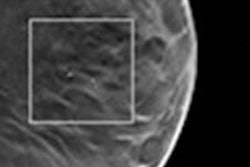

Marco Stampanoni, PhD, from ETH Zurich and the Paul Scherrer Institut in Switzerland, described an approach that he and his colleagues have developed, which exploits the complementary nature of microcalcification absorption and small-angle scattering signals obtained simultaneously with an x-ray grating interferometer on a conventional x-ray tube.

If confirmed, the new method would allow discrimination between type I (green) and type II (red) microcalcifications in a noninvasive way.The method relies on the observation that some microcalcifications show opposite absorption and small-angle scattering signals. The novel technique is highly sensitive to the morphological and structural information of the microcalcifications, where conventional absorption-based x-ray mammography is not.

Marco Stampanoni is professor for x-ray imaging at ETH Zurich and head of the tomography group of the Swiss Light Source at the Paul Scherrer Institut in Switzerland.The researchers initially studied whole-breast samples obtained from patients who had undergone mastectomies after being diagnosed with invasive breast cancer. They are currently testing their hypothesis that the positive predictive value (PPV) of phase-contrast x-ray imaging using Talbot-Lau grating interferometry is two times larger than that of conventional mammography, using biopsy samples of 20 patients with suspicious microcalcifications undergoing vacuum-assisted breast biopsy.